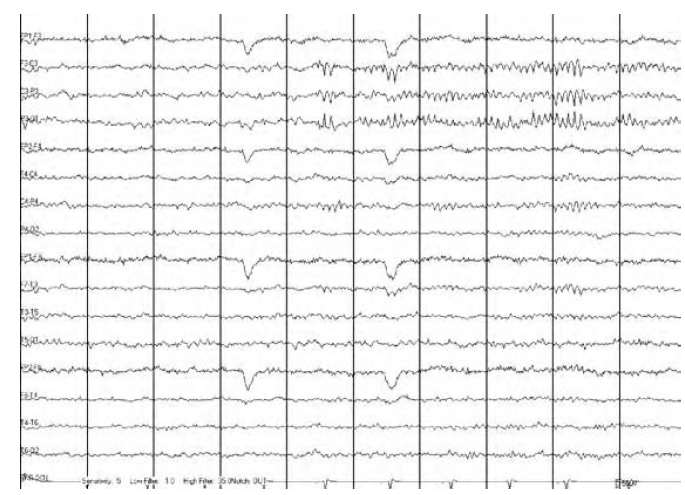

AT WHAT STAGE OF SLEEP?

The above EEG shows a simple partial seizure that occurred out of stage 2 sleep.